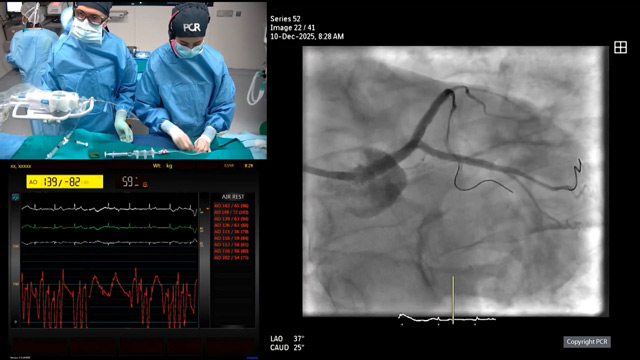

Left main - LIVE Case

10 Dec 2025 – From GulfPCR-GIM 2025

This session delivers an in-depth exploration of left main coronary artery intervention, featuring a live educational case from the Mohammed Bin Khalifa Bin Salman Al Khalifa Specialist Cardiac Centre in Awali, Bahrain. Attendees gain insights into the pivotal role of computed tomography and intravascular imaging in...